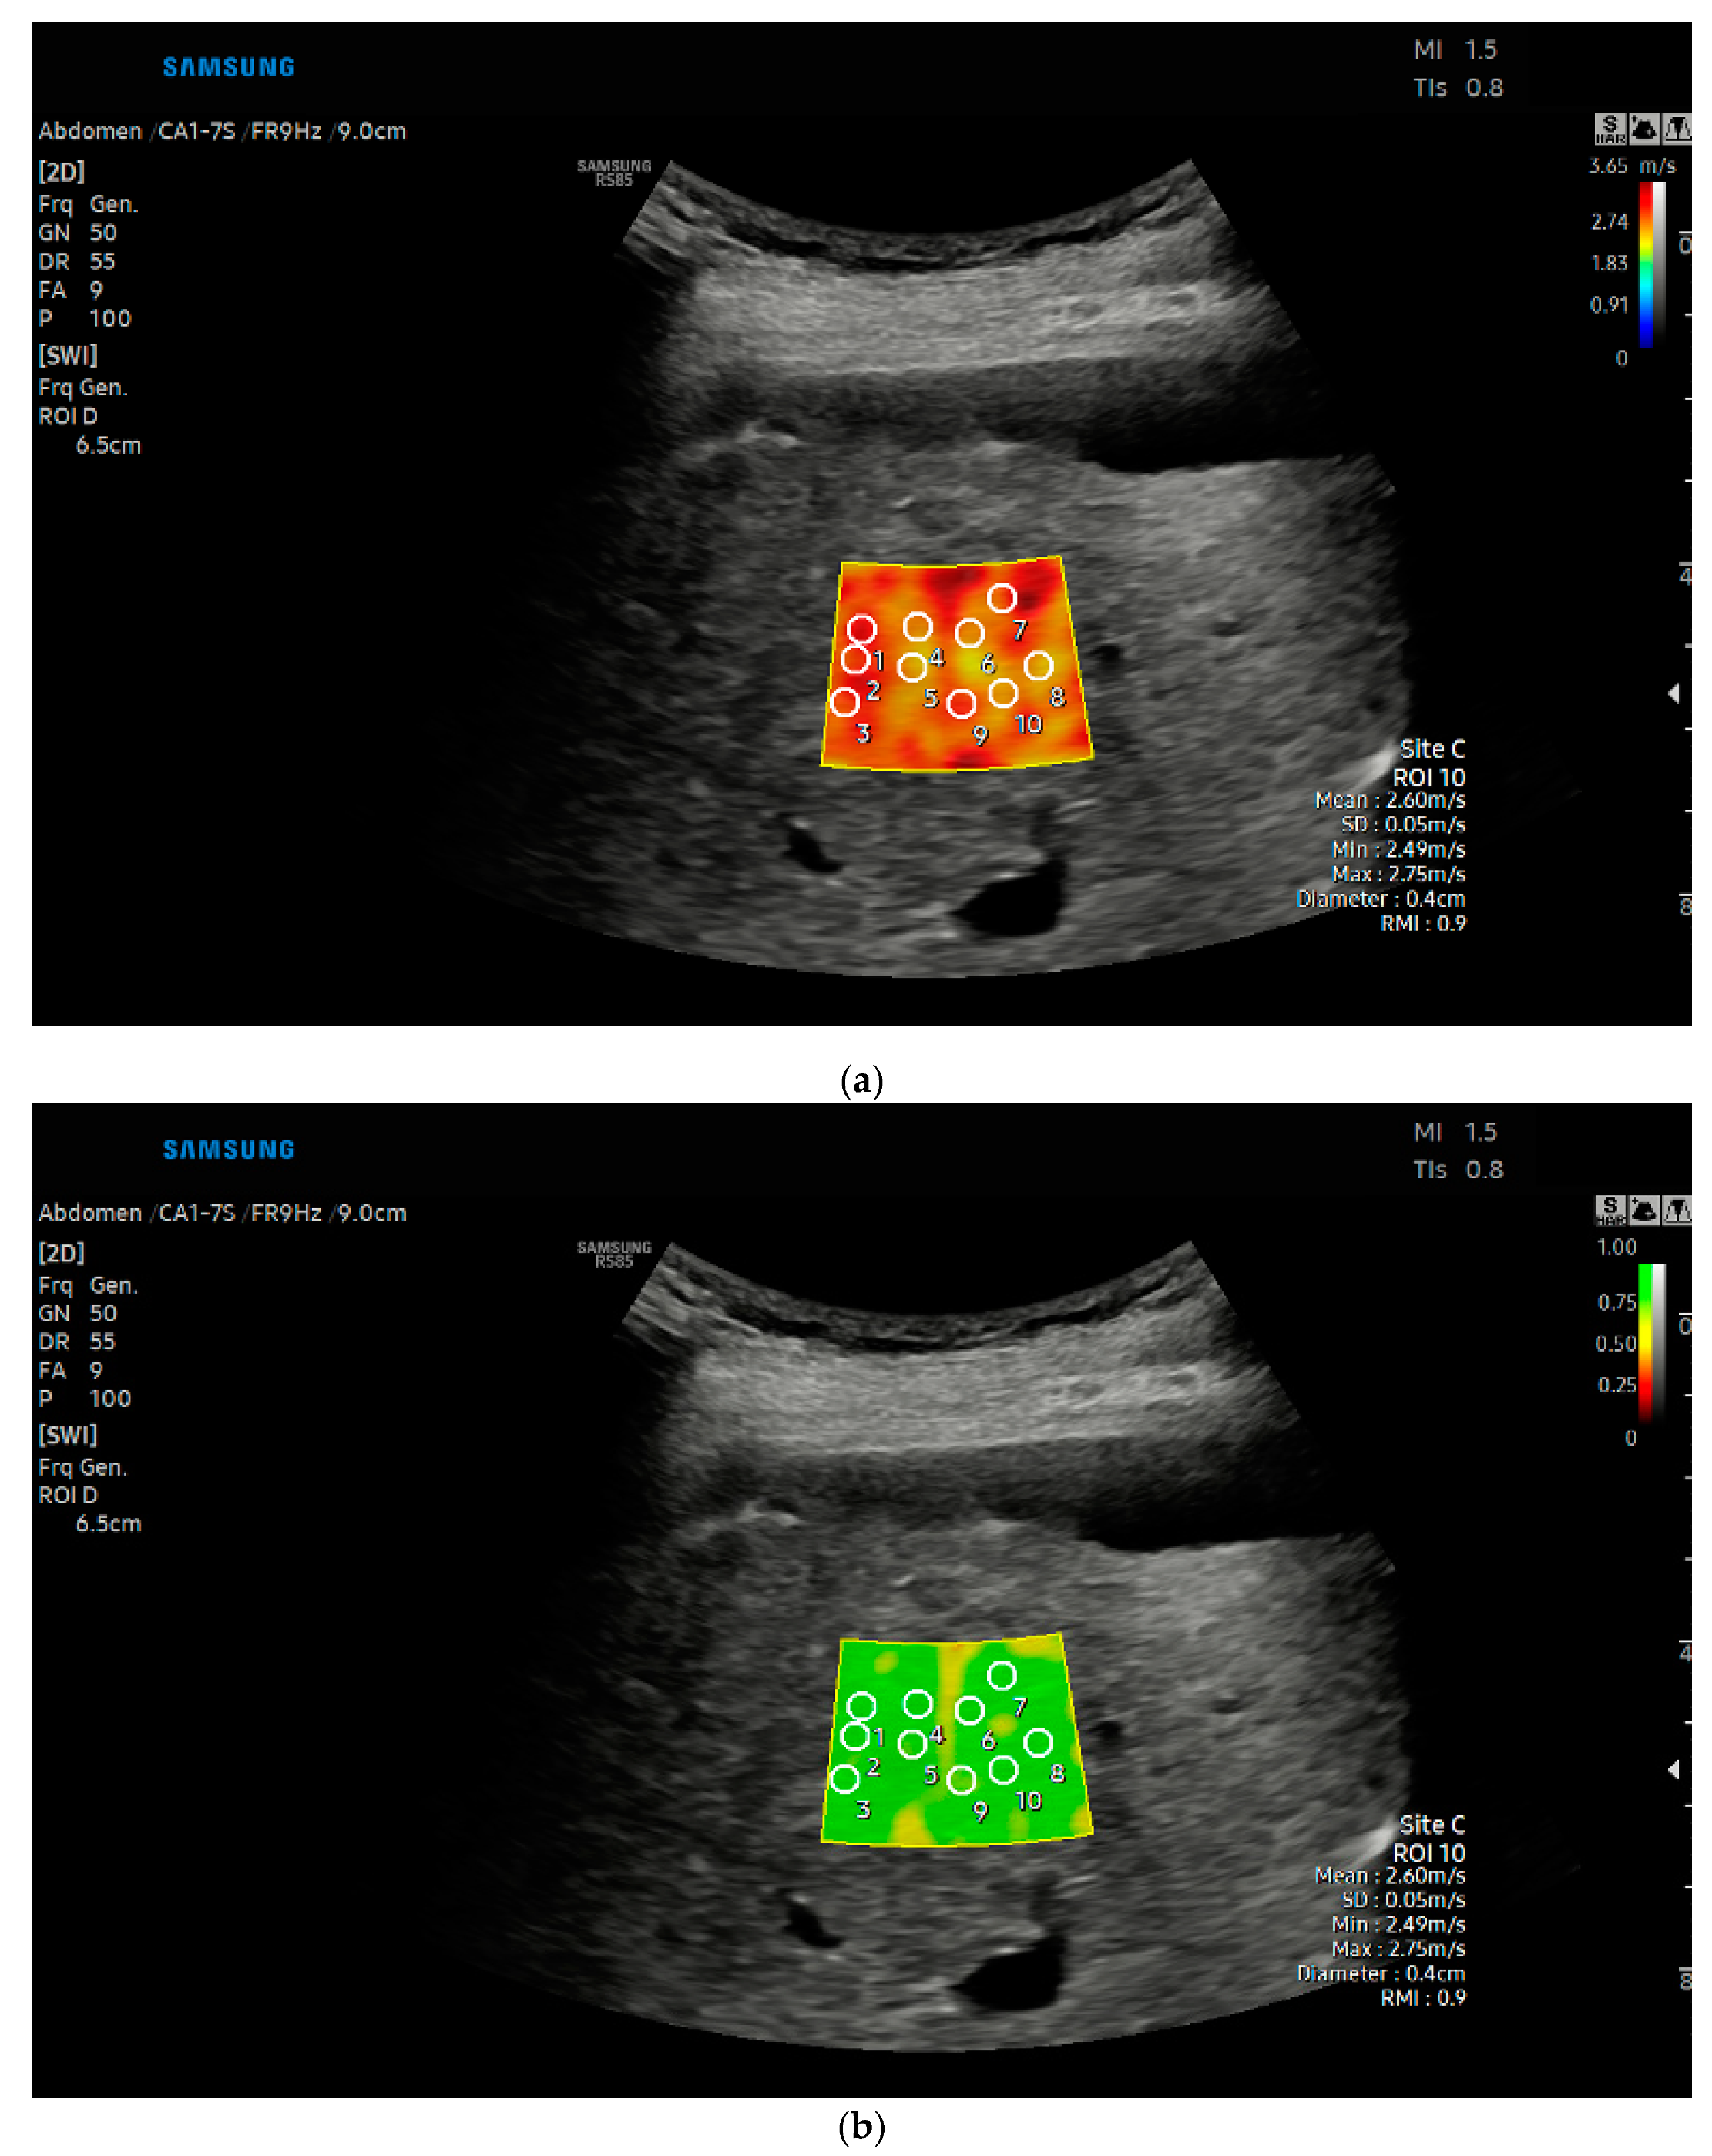

2.2. Liver Stiffness Measurements with Shear Wave Elastography